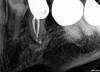

Fig 9 and Fig 10. Modern microsurgical techniques enhance the success rate of surgical retreatment through improved magnification, illumination, and the creation of optimal preparation and root-end filling. Fig 9: Postoperative periapical radiograph following apical surgery. Fig 10: Periapical radiograph at 18-month follow-up showing bony healing.

Figure 9

Fig 10. Modern microsurgical techniques enhance the success rate of surgical retreatment through improved magnification, illumination, and the creation of optimal preparation and root-end filling. Fig 9: Postoperative periapical radiograph following apical surgery. Fig 10: Periapical radiograph at 18-month follow-up showing bony healing.